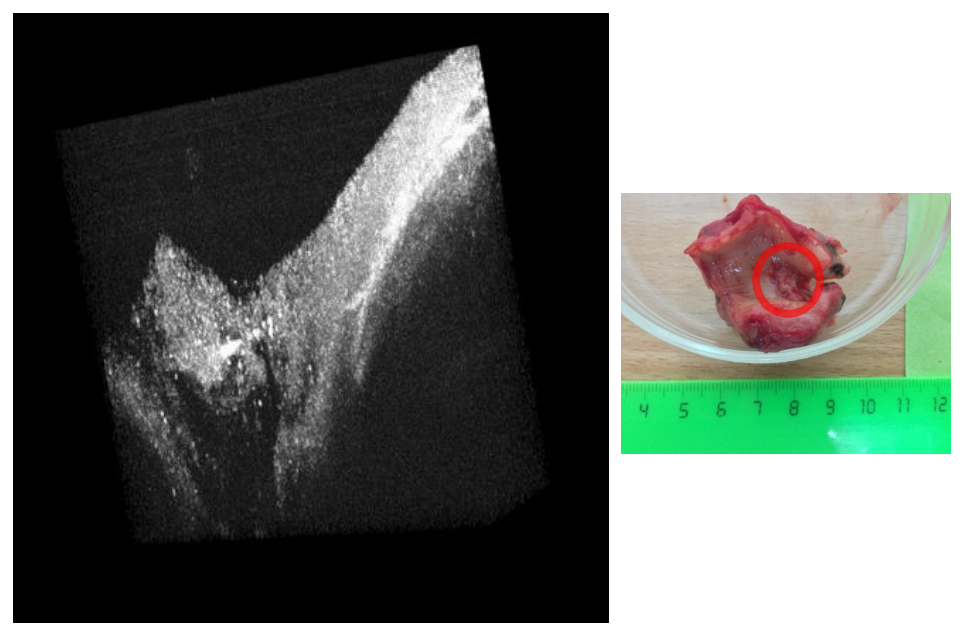

В Самарском университете данный подход использовали для исследования тканей кожи и легкого с онкологическими образованиями. На фото слева — восстановленное 3D-изображение тканей легкого. А справа — фотография участка, с которого происходила регистрация сигнала.

На картинке слева заметно различие структур между собой. Черное — это воздух, оттуда сигнал не приходил. Пористая структура, похожая на губку, — это здоровая ткань легкого. При переходе вправо можно наблюдать, как возникают слои. Они более плотные и имеют определенную структуру, которая характерна для онкологических новообразований в тканях легкого. Это пример плоскоклеточного рака, удаленного в результате операции в Самарском онкологическом центре.